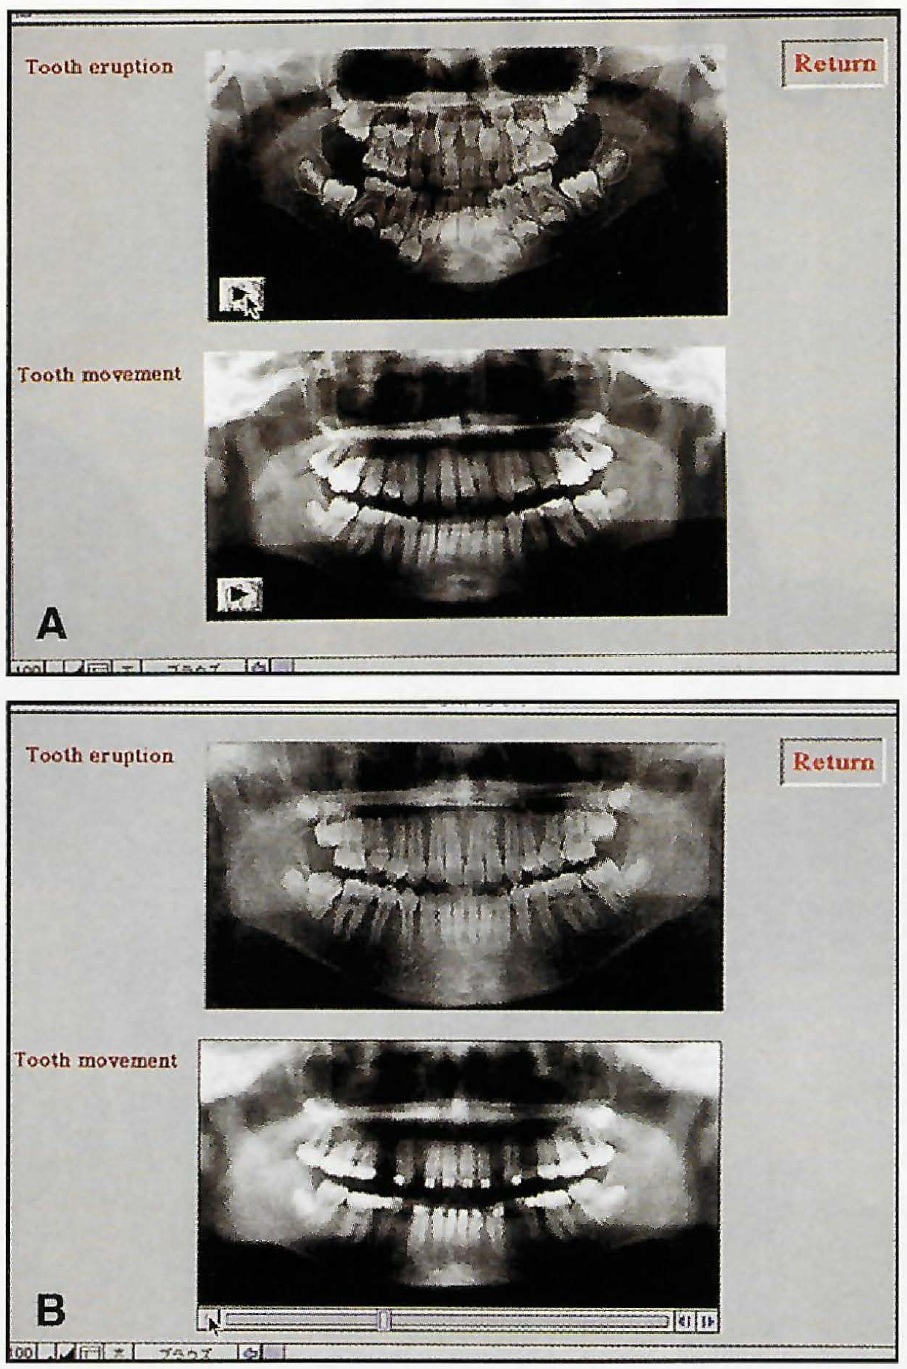

A 23-year-old female patient presented with the chief complaint of protrusive upper anterior teeth (Fig. 1A and B).

Fig. 1 A. 23-year-old female patient with Class II canine relationship, protrusive upper anterior teeth, and anterior open bite before treatment (continued in next image).

Fig. 1 (cont.) B. Initial ClinCheck* records.

The upper right lateral incisor was congenitally missing, and the upper left first premolar had been extracted at age 15, during previous orthodontic treatment with fixed appliances. An anterior open bite had resulted from a protrusive tongue habit acquired after that treatment. The canine relationship was Class II.

The patient requested an esthetic improvement using Invisalign clear aligners. Our treatment plan involved extraction of the lower left and both upper third molars, followed by distal movement of the upper molars. Because the patient lacked an upper right lateral incisor, the upper right first premolar would serve as the canine and the upper right canine would be recontoured as the lateral incisor after orthodontic tooth movement.

After five weeks of treatment, the upper second molars had been distalized, and distal movement of the first molars was initiated (Fig. 4).

Fig. 4 Sequential distalization. A. Distalization of second molars completed after five weeks of treatment. B. Distalization of first molars completed after three months of treatment. C. Distalization of premolars completed after five months of treatment. D. Distalization of canines completed after seven months of treatment. E. Upper anterior retraction completed after 10 months of treatment.

Class II elastics were continued to prevent anchorage loss. Distalization of the first molars required nine weeks, followed by eight weeks for the premolars and five weeks for the canines. After 10 months of treatment, when anterior retraction was complete, a gingivoplasty was performed in the upper right anterior region to achieve esthetic symmetry of the gingival margins, and the upper right canine was recontoured to simulate a lateral incisor (Fig. 5).